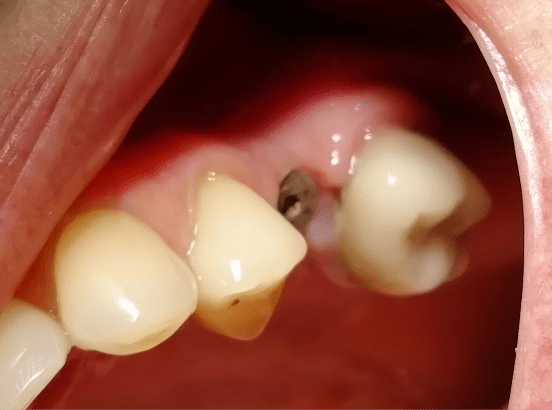

Фотографии до и после: Имплантация

На странице представлено портфолио стоматологий Омска с фото работ до и после имплантации зубов. Мы собрали разные клинические случаи: одиночные импланты, восстановление нескольких зубов и полная реконструкция зубного ряда. Здесь вы можете видеть, как выглядят восстановленные зубы, меняется форма улыбки после процедуры. Изучите результаты до и после имплантации зубов, чтобы оценить качество работы врачей и выбрать стоматологию в Омске, которая поможет вернуть функциональность и эстетику вашей улыбке.

Имплантация

Доктор: Добычин Михаил Сергеевич

Одномоментная имплантация

Доктор: Добычин Михаил Сергеевич

Одномоментная имплантация

Доктор: Вальчук Олег Владимирович

Установка импланта Osstem

Доктор: Мальцев Дмитрий Владимирович